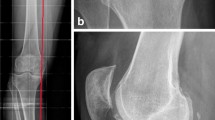

This study was conducted to examine the long-term survivorship and functional outcome of distal femoral varus osteotomy with fresh osteochondral allograft following failed lateral tibial plateau fracture surgery. We hypothesized that this procedure would be associated with a low rate of conversion to total knee arthroplasty (TKA) at medium to long-term follow-up.

A consecutive series of 27 of distal femoral varus osteotomy combined with fresh osteochondral allograft following (27 patients) conducted between January 1981 and January 2005 for failed lateral tibial plateau fracture was retrospectively reviewed. Outcome measures included the Knee Society Knee Score (KSKS) and Knee Society Function Score (KSFS) and conversion rates to TKA.

The study group consisted of 15 females (55.6 %) and 12 males (44.4 %), with a median age of 41.2 years (range 17–62 years). The median follow-up was 13.3 years (range 2–31 years). The knee function scores improved significantly at 2 years post-surgery (p < 0.01) from a median of 54.6 points preoperatively to 83.8 points (KSKS) and median of 50.6 points to 71.1 points (KSFS) at 2 years post-distal femoral varus osteotomy with fresh osteochondral allograft following surgery. At most recent follow-up, 4/27 patients had required conversion to TKA, and one patient had fractured the FOCA, requiring revision of the allograft. The survivorship for distal femoral varus osteotomy with fresh osteochondral allograft following was 88.9 ± 4.6 % at 10 years, 71.4 ± 18.1 % at 15 years, and 23.8 ± 11.1 % at 20 years.

The use of distal femoral varus osteotomy combined with fresh osteochondral allograft following in patients with failed lateral tibial plateau fracture results in the majority of patients having good or excellent clinical outcomes and significantly delays the need for TKA in most patients.